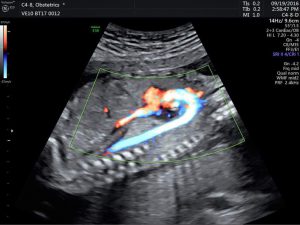

Siêu âm thai là kỹ thuật chẩn đoán y khoa bằng hình ảnh giúp theo ...

Ngày nay, với sự phát triển của công nghệ y học cho phép mẹ nhìn ...